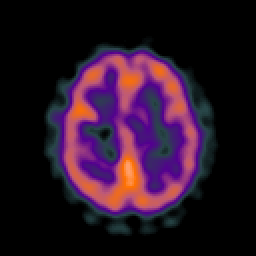

AIDS dementia: overlay -- Slice #12

[Home][Help][Clinical][Tour 1] Slice 12